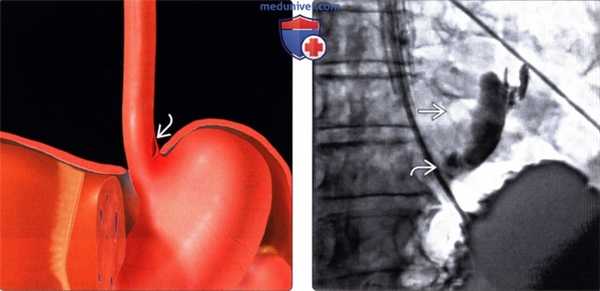

(Слева) На рисунке показан вертикальный разрыв стенки дистальных отделов пищевода, непосредственно над воротами диафрагмы и областью пищеводно-желудочного перехода.

(Справа) На рентгенограмме пищевода, полученной при рентгеноскопии после введения водорастворимого контрастного вещества через назогастральный зонд, определяется утечка контраста SB через поврежденный участок в области левой передней стенки дистального отдела пищевода - типичные изменения при синдроме Бурхаве. (Слева) На аксиальной КТ с контрастным усилением, выполненной мужчине среднего возраста, предъявляющего жалобы на сильную боль в груди, появившуюся после повторной рвоты, визуализируется газ и контраст вне просвета пищевода, в окопопищеводных тканях и в нижнем средостении, верхних отделах брюшной полости.

(Справа) На рентгенограмме пищевода, полученной при рентгеноскопии после введения водорастворимого контрастного вещества через назогастральный зонд, определяется утечка контраста SB через поврежденный участок в области левой передней стенки дистального отдела пищевода - типичные изменения при синдроме Бурхаве.